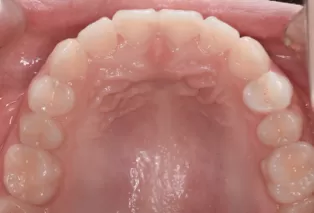

Photos intra-orales